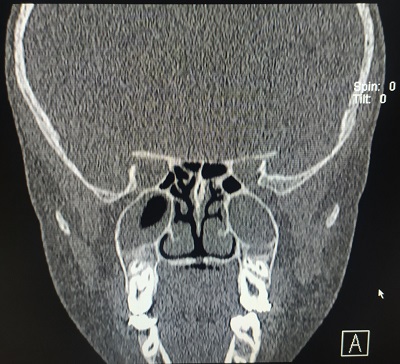

Paciente de 12 años, que acude a la revisión programada de salud. Presenta peso y talla acordes con su evolución previa, en percentil 10. En la exploración destaca úvula bífida. Se pide a la paciente que emita varios sonidos, apreciándose un hundimiento en V de la porción posterior al paladar duro. Destaca habla hipernasal. El resto de la exploración es normal. Refiere buen rendimiento escolar y está bien integrada con sus compañeros. De procedencia marroquí sin antecedentes de consanguinidad. Se revisan los antecedentes personales de la paciente enfocados a sospecha de fisura palatina, no existiendo en su historial episodios de regurgitación nasal con la ingesta. Destacan dos episodios de otitis medias agudas. Figura haber consultado por sensación de obstrucción nasal. Con 10 años fue valorada por odontología por malposicion de piezas dentarias, derivándola al ortodontista. Se remite al Servicio de Otorrinolaringología. En la exploración destaca úvula bífida, velo del paladar óseo normal a la palpación, sin observarse separación de línea media. En la fibroscopia nasofaríngea se aprecia desviación nasal con convexidad hacia fosa nasal izquierda con un cavum normal. La endolaringe es normal. Se solicita una tomografía axial computarizada facial/senos paranasales sin contraste, donde destaca: “Ausencia de neumatización del seno frontal derecho. Hallazgos sugerentes de cambios inflamatorios sinusales. Defecto de fusión óseo en línea media del paladar duro que afecta prácticamente a toda su extensión anteroposterior, cubierto por tejido de partes blandas. Hallazgos sugerentes de fisura palatina ósea, cubierta por mucosa” (Fig. 1). Se deriva al Servicio de Cirugía Maxilofacial de referencia.

Figura 1. Imagen de la tomografía axial computarizada

Figura 1. Imagen de la tomografía axial computarizada.